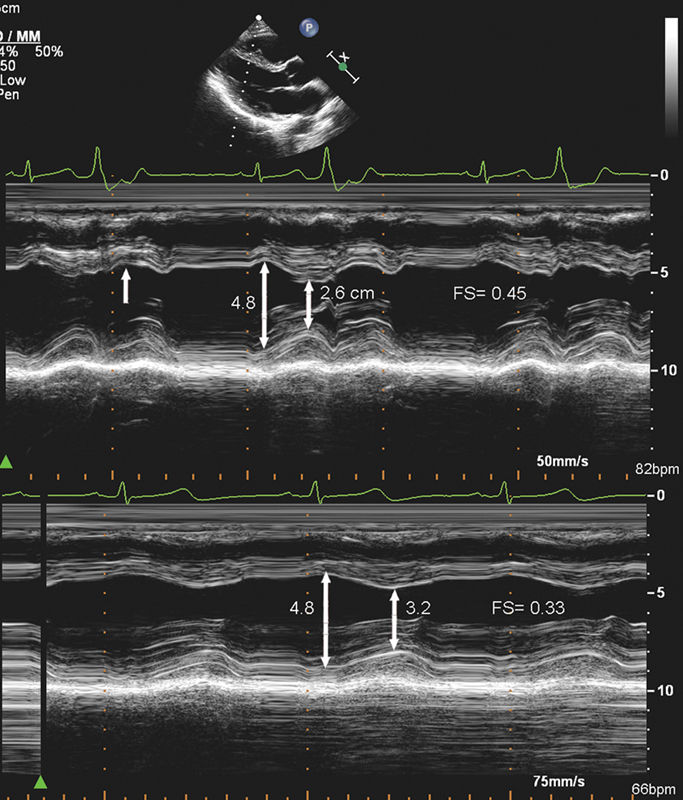

فحوصات تشخيصية لبعض امراض القلب والشرايين التاجية